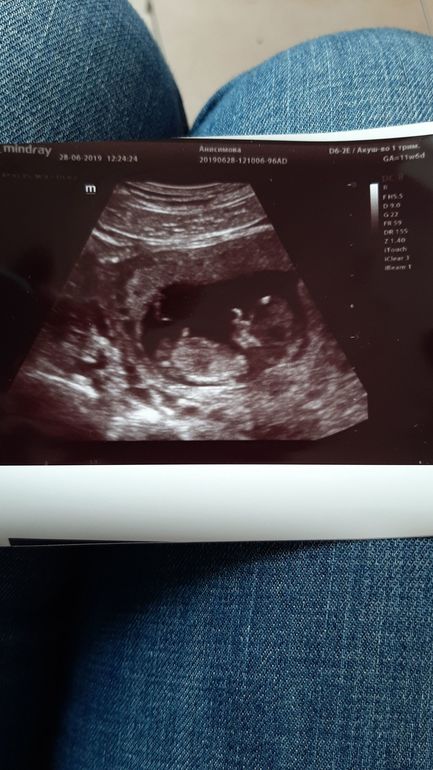

1 скрининг пройден. Ура!!!

А по узи все прекрасно. Малышка у нас будет на 80%. С сыном пол даже на 22 неделях не предполагади. А тут сразу сказали. Говорят этот врач всегда пол говорит верно. Будем надеяться. Что будет у нас еще и принцесса Алиса). Фотку таки сделали. И не за 200 руб а за 125😂. Так что ждем результаты крови и второго скрининга.

Прикрепление в этот раз по передней стенке,наверное поэтому и вылез так рано пузик. Сын был по задней. Пуз вылез ток на 20й неделе. Фото прикреплю. Нижнее.